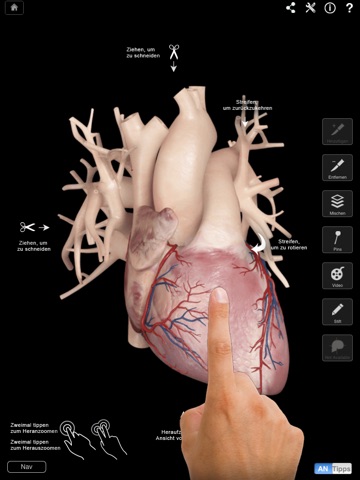

• 360-3D-Grad-Rotation jedes Körperteils in der Horizontale - mit einer Wischbewegung.

• Drehung in der Vertikale für Ansicht von oben und unten.

• Graphische Hinweise: Hinweise auf dem Bildschirm, die ein- oder ausgeschaltet werden können, für ein komplettes Verständis aller Bestandteile der App.

Doppeltes Tippen für Zoom - durch Tippen auf den Bildschirm können Sie jede Ansicht vergrößern.